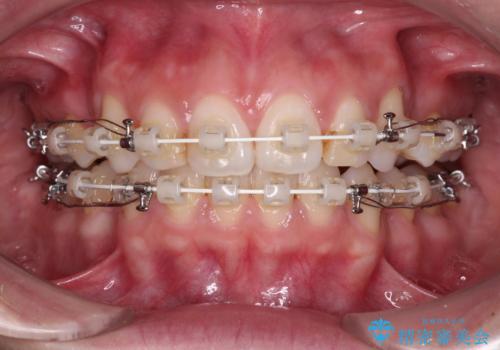

- 矯正装置

- 審美装置

- 1年7ヶ月

- 10-30回

上下左右第一小臼歯4本を抜歯して、積極的に口元を引っ込めるよう、ワイヤー装置にて矯正治療を行うこととしました。